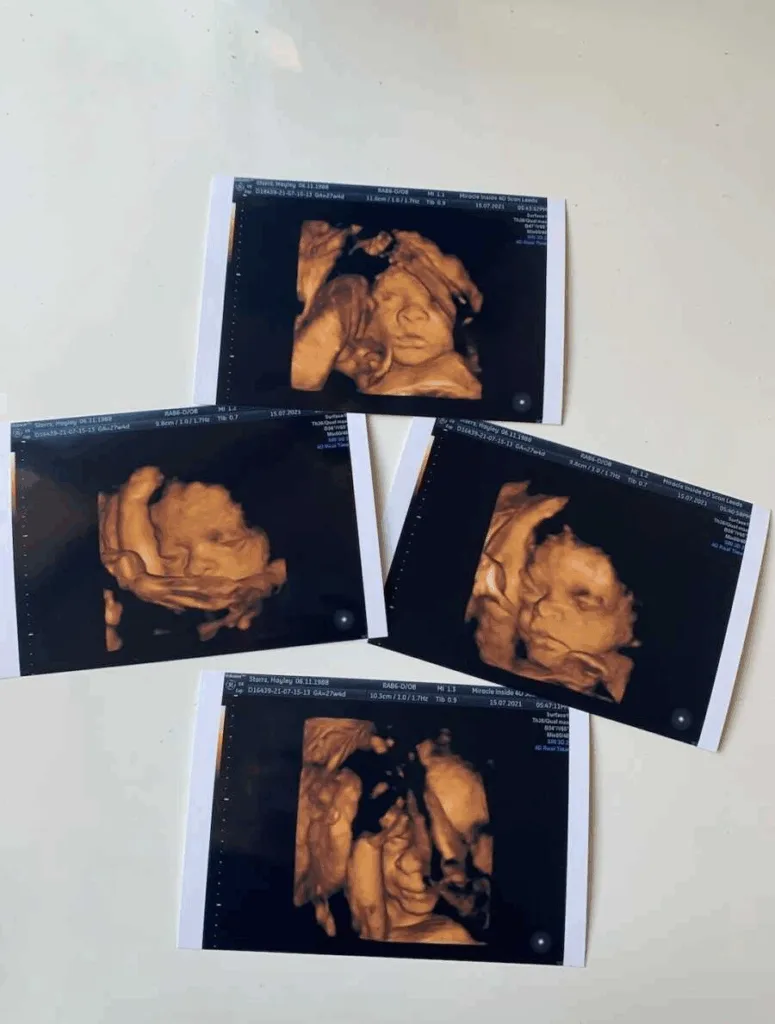

Motherhood changed the center of gravity. Her story became his from the day she saw the positive test on January 31, 2021, during the UK’s lockdown. She and Reece, newly living together, were surprised and thrilled that it happened so quickly. A private scan at 16 weeks told them they were having a boy, and they celebrated with family, moved to a bigger place, and shared the news after the 12-week scan, believing the road ahead would be straightforward. Around 26 weeks, Hayley noticed Ollie’s movements felt off, slower, and irregular. They went to the maternity assessment several times. Every time, the staff told them he was fine; his heart rate looked good. Still, her worry didn’t lift. At 37 weeks, she asked for a scan to check the cord and placenta; it also appeared normal.